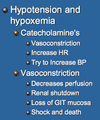

Review Card: Pathophysiology of Gastric Dilatation Volvulus

Respiratory System: Increased CO2, Respiratory Acidosis

Cardiac System- Decreased Preload and Afterload, Arrhythmias

Gastric System- Mucosal Sloughing, Bacterial Translocation